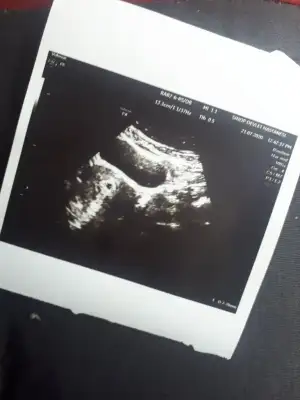

Keseyi gördük ama haftaya gel dedi kalp atışını duyarsak sıkıntı yok dedi ama duymazsak kimyasal gebelik dedi

Kesem bu 13.3 cm yaziyor

• 20200721_120409.webp